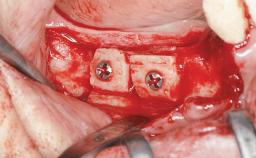

Iliac and Calvarial Bone Blocks for Onlay Grafting of a Severely Resorbed Edentulous Maxilla

A 45-year-old woman with a completely edentulous maxilla was referred to evaluate the possibility of rehabilitation with an implant-supported prosthesis. This patient was healthy and a non-smoker. She had been wearing a maxillary complete denture opposing a natural mandibular dentition since her twenties. This situation had resulted in progressive resorption of the alveolar ridge, repeatedly creating a need for relining the denture. Twenty years later, despite multiple adaptations and the use of “glues” the denture was unstable and causing the patient psychological and functional discomfort.

Bone Augmentation Horizontal|Sinus Floor Elevation|Staged|Vertical

Augmentation Materials Autogenous chips|Autogenous block(s)

Bone Volume Deficient vertically or deficient vertically AND horizontally